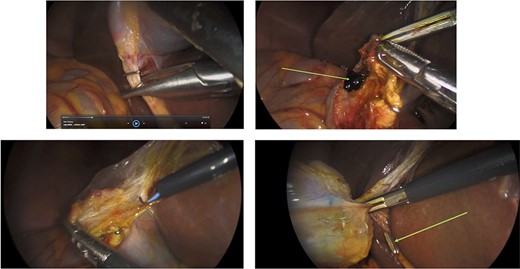

Surgery: laparoscopic cholecystectomy. (a) clipping of the common bile duct. (b) retrograde dissection of the fundus of the gallbladder. (c) iatrogenic gallbladder injury and spillage of pigment stones (green arrow). (d) completion of the retrograde dissection with visualization of the cystic duct stump (green arrow).

Surgery: gastric wedge resection. (a) laparoscopic entry into the lesser sac through the gastro-colonic ligament (blue arrow). (b) methylene blue markings visible on the serosal layer of the stomach (blue arrows) to delineate the tumour margins. (c) complete mobilization of the gastro-colic and gastro-splenic ligament and visualization of the gastric GIST (green arrow) on the posterior wall of the stomach. (d) macroscopically clear tumour margins post GIST resection. (e) posterior gastric wall sutured closure (yellow arrow).

An elective gastroscope showed a soft tissue mass on the posterior wall of the body of the stomach (Fig. 2a). This appeared to be an underlying submucosal tumour with no mucosal involvement. Biopsies taken showed a normal mucosa with no malignant or premalignant mucosal pathology. A complete pathological diagnosis could not be ascertained and after an extensive discussion with the patient and her family, conservative management was contemplated rather than a surgical resection. Her symptom profile did not fit clearly with either biliary colic or a gastric GIST. Three months later the patient returned to consider surgery as the pain was not subsiding. She had a second gastroscope to mark the tumour margins with methylene blue as part of her workup for a laparoscopic gastric wedge resection (Fig. 2b). The mucosa over the lesion now showed an ulceration which we ascribed to excessive tumour growth (Fig. 2c). She also requested a concomitant laparoscopic cholecystectomy as we could not clearly elucidate the aetiology behind her abdominal pain. An informed consent was signed along with permission to record the surgical procedure. The laparoscopic cholecystectomy, initially performed, was uneventful. This was a combined antero-retrograde cholecystectomy (Fig. 3a–d). The greater curvature of her stomach was mobilized laparoscopically until the lesion was clearly visualized on the posterior wall with the aid of the methylene blue dye injected at endoscopy (Fig. 4a–c). The decision was then made to convert to open surgery and the lesion excised with a 1 cm margin (Fig. 4d). The gastrotomy wound was closed in two layers with a 2–0 polydioxanone absorbable running suture (Fig. 4e). Her physiological recovery was unremarkable, and she was discharged home on post-operative Day 5. Pathology confirmed the presence of a gastric GIST with clear surgical margins. Gallbladder pathology showed a chronic cholecystitis and pigment stones (Fig. 5).